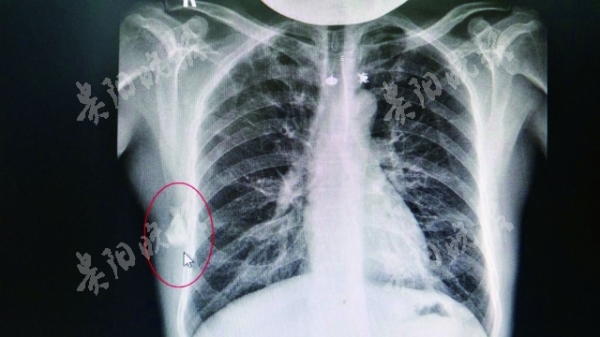

“CT顯示,他背部肩胛骨下方有異物,但并不確定是什么物體。”該院外科執行主任柏帆說,結合鄭發興此前摔傷的病史,醫生懷疑這塊異物應為6年前摔傷留下的。

5月23日,醫院為鄭發興實施了手術,從離他肺部僅2厘米左右的地方,取出了一塊一端非常尖銳的碎玻璃片。

據柏帆主任介紹,由于在體內“寄居”多年,這塊玻璃所在位置的肌肉組織已經形成一個自我保護的“小包塊”,讓鄭發興過去幾年沒有明顯痛感,但玻璃片將這個小包塊割破后,鄭發興的背部便有了疼痛。(記者 黃寶華 )